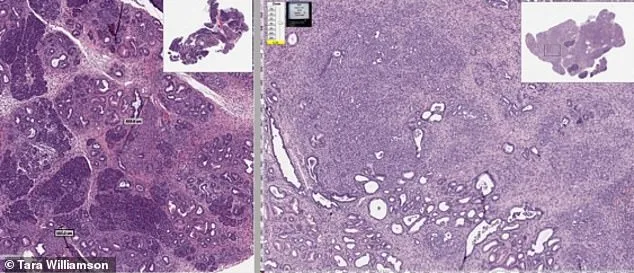

The patent's focus on polymorph C has drawn attention from researchers. Pharmaceutical compounds often exist in multiple solid forms, each with different absorption rates. The patent states formulations with 90% or more polymorph C deliver the drug more effectively, potentially boosting its cancer-fighting power. Scientists believe the drug attacks tumors by disrupting proteins cancer cells rely on for growth, reducing blood vessel formation, and triggering apoptosis—the body's natural cell-destroying process. This multi-pronged approach could make mebendazole a valuable tool in treating aggressive cancers like brain tumors.